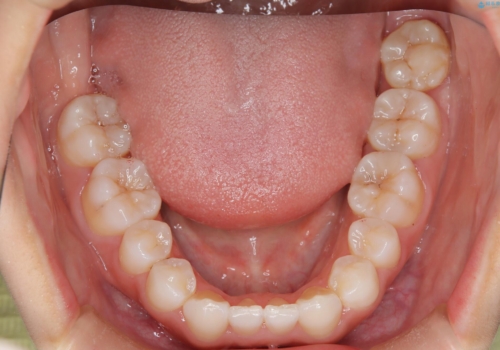

- 子供のころに矯正治療をされていたが、後戻りをしてしまったという20代女性の患者様です。上顎左右の2番が、咬合時に下顎の歯よりも内側に入っているクロスバイトという状態でした。奥歯の咬合関係は変えずに、マウスピース矯正にて前歯の並びを綺麗なアーチに仕上げました。再度後戻りしてしまうリスクを軽減させるために、リテーナー(保定装置)をお渡ししています。